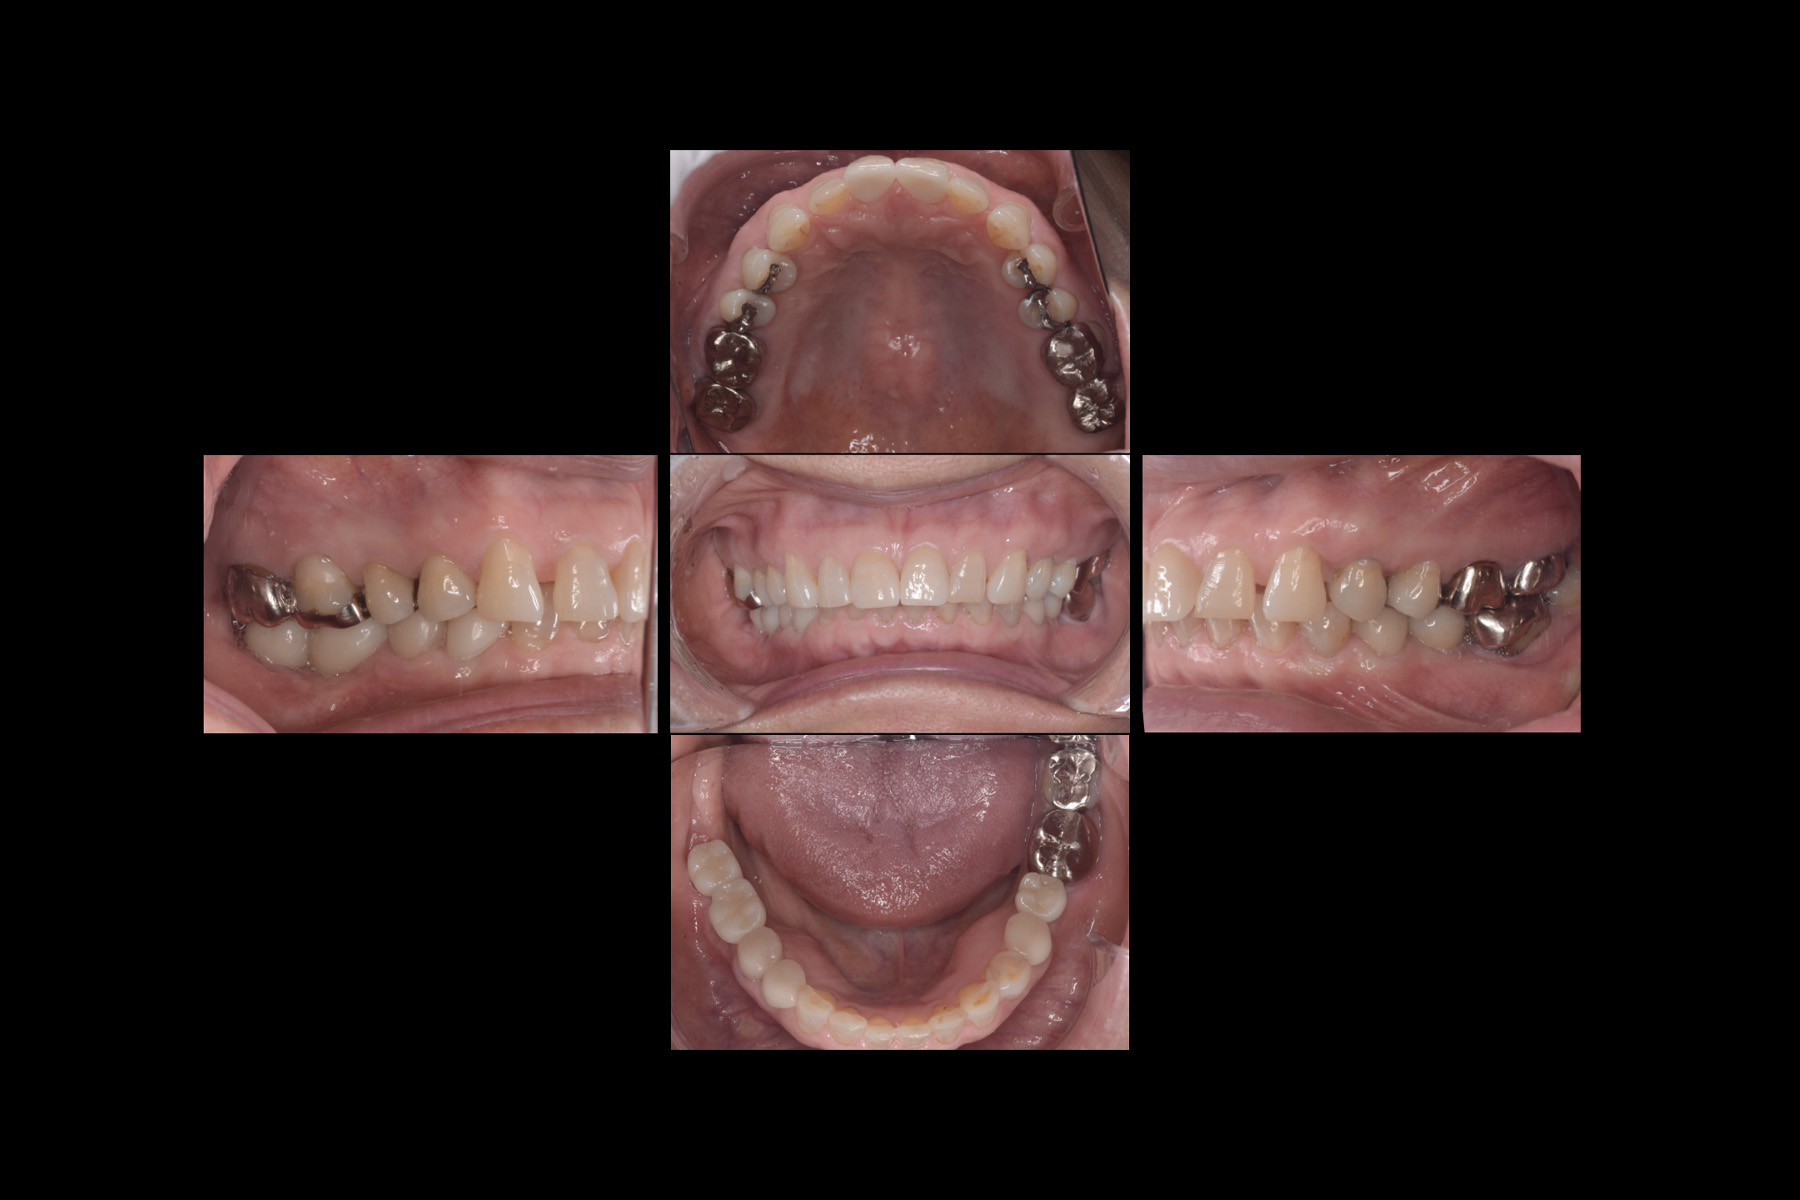

- 主訴

- 欠損部と前歯部の審美不良

- 治療内容

- 角化歯肉も足りないため歯肉移植も同時に行っているケース。

欠損部と前歯部の審美不良を主訴に来院されました。

機能と審美の両問題を解決しました。